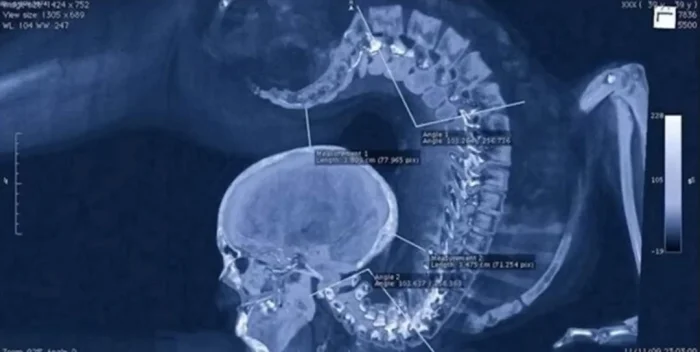

19. «Рентгеновский снимок зубов моего шестилетнего ребёнка»